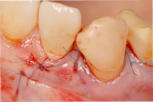

2. Transplantate für Zahnfleisch und Bindegewebe:

Durch Transplantate kann verlorenes Gewebe wieder aufgebaut werden. Damit wird eine dauerhafte Stabilität der Gewebe und damit auch des Knochens erzielt und eine gute Putzfähigkeit für Zähne oder Implantate erreicht. Beispiele:

Mikrochirurgischer Wundverschluss

Gingivatransplantat fixiert

Zustand 3 Wochen post OP